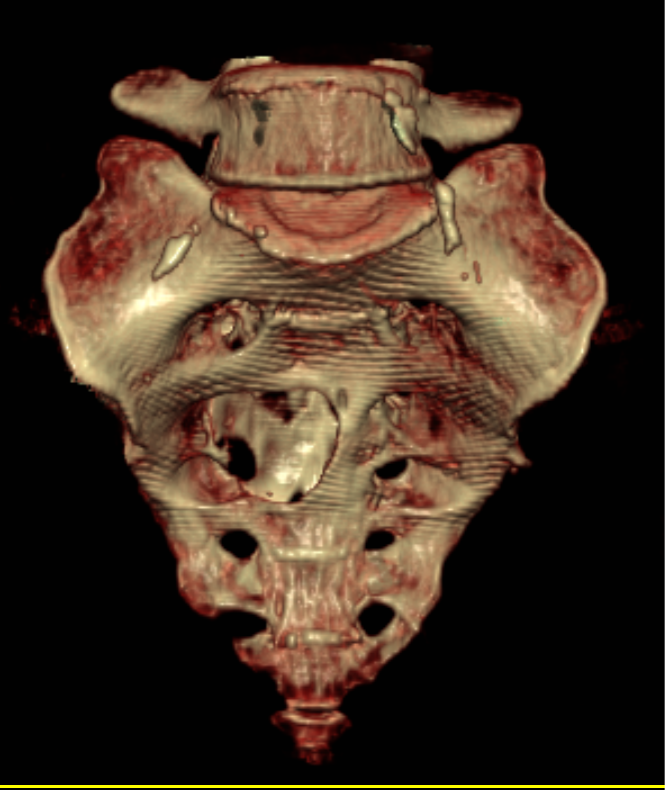

(CT三维重建)